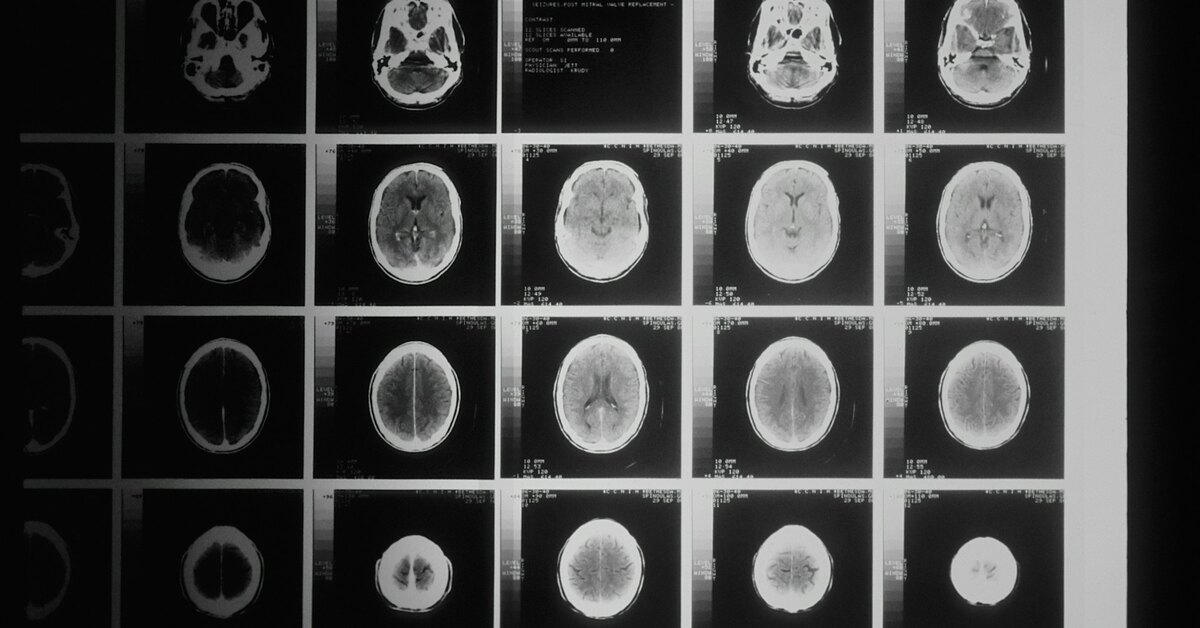

Ученые определили биологическую основу шизофрении

Команда из Королевского колледжа Лондона выяснила, что у людей с шизофренией в мозге снижен уровень железа и миелина – вещества, которое изолирует нервные волокна. Эти отклонения нарушают передачу сигналов между областями мозга и могут объяснять проблемы с мышлением и поведением. Главная причина, по мнению ученых, – сбои в работе клеток, отвечающих за производство миелина. Они не усваивают достаточно железа, а значит, не создают нужную «изоляцию» для нейронов.